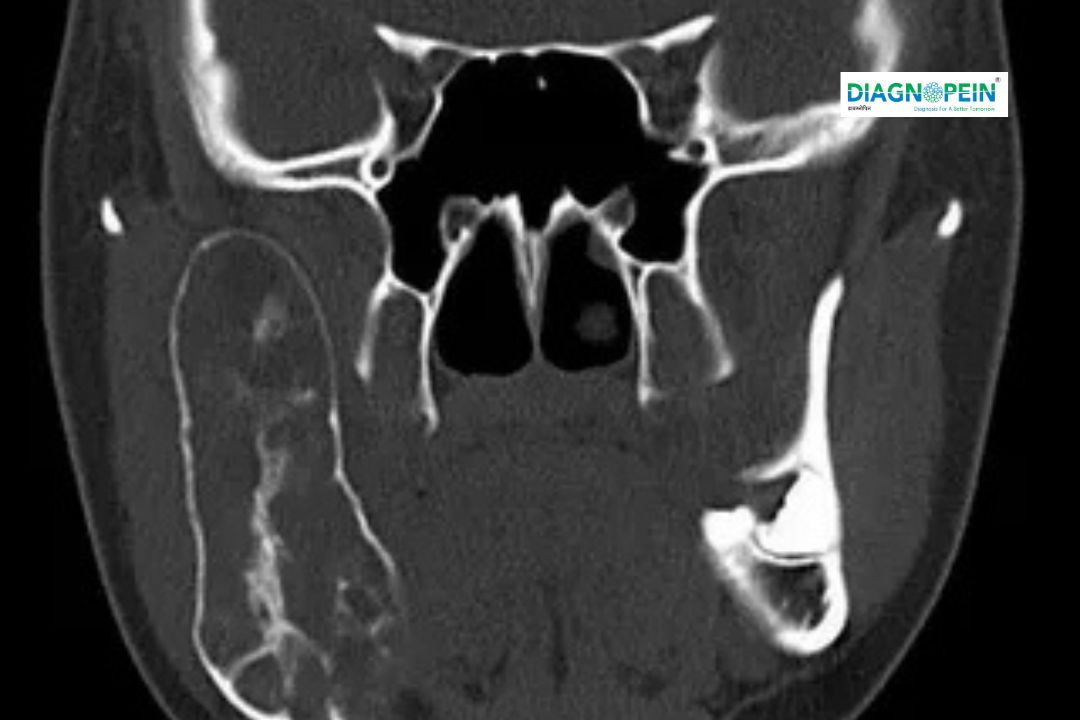

A CT Mandible with 3D imaging is a specialized, non-invasive diagnostic test that uses X-rays to produce highly detailed cross-sectional and three-dimensional images of the lower jawbone (mandible). This scan enables doctors to accurately assess complex bone structures, detect fractures, tumors, cysts, infections, and other abnormalities that conventional X-rays may miss. The 3D reconstruction allows visualization of the mandible from multiple angles, providing vital information for diagnosis and surgical planning, such as dental implant placement or trauma treatment.

CT (Computed Tomography) of the mandible is a non-invasive diagnostic test that uses X-rays to create cross-sectional images of the jawbone. The 3D reconstruction feature digitally models these images to visualize complex bone anatomy from multiple angles. This helps clinicians identify problems that might not be visible on routine X-rays.